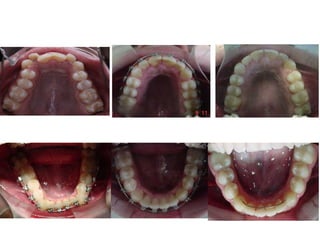

Classe I | Overbite | Mordida Cruzada Post-direita | Mordida Aberta 12/43

DM = - 10,2 mm Spee = -3 mm DC = - 1,6 mm IMPA 88°

18a 3m

Elementos de Diagnóstico

Perfil Mole Facial Convexo | Padrão Vertical | Nariz Proeminente

Assimetria Discreta | Linha do Sorriso Adequada

Planejamento

XP 18, 28, 38 e 48

Aparelhos Fixos Autoligantes

Passivos “Damon High”

slot .022”

1)N/A (arcos red. NiTi TA)

2)2 mm de Desgastes

interproximais 33 a 43

3)Arcos ret. Niti

4)Intercuspidação

5)Finalização (arcos ret. Aço

inox.)

6)Remoção e Contenções